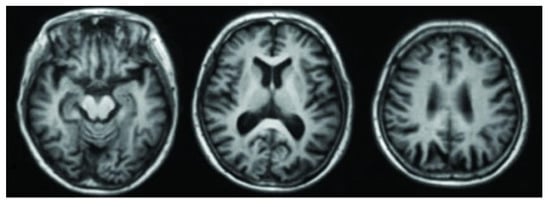

3.1. Magnetic Resonance Imaging (MRI)

3.2. Functional Magnetic Resonance Imaging (fMRI)